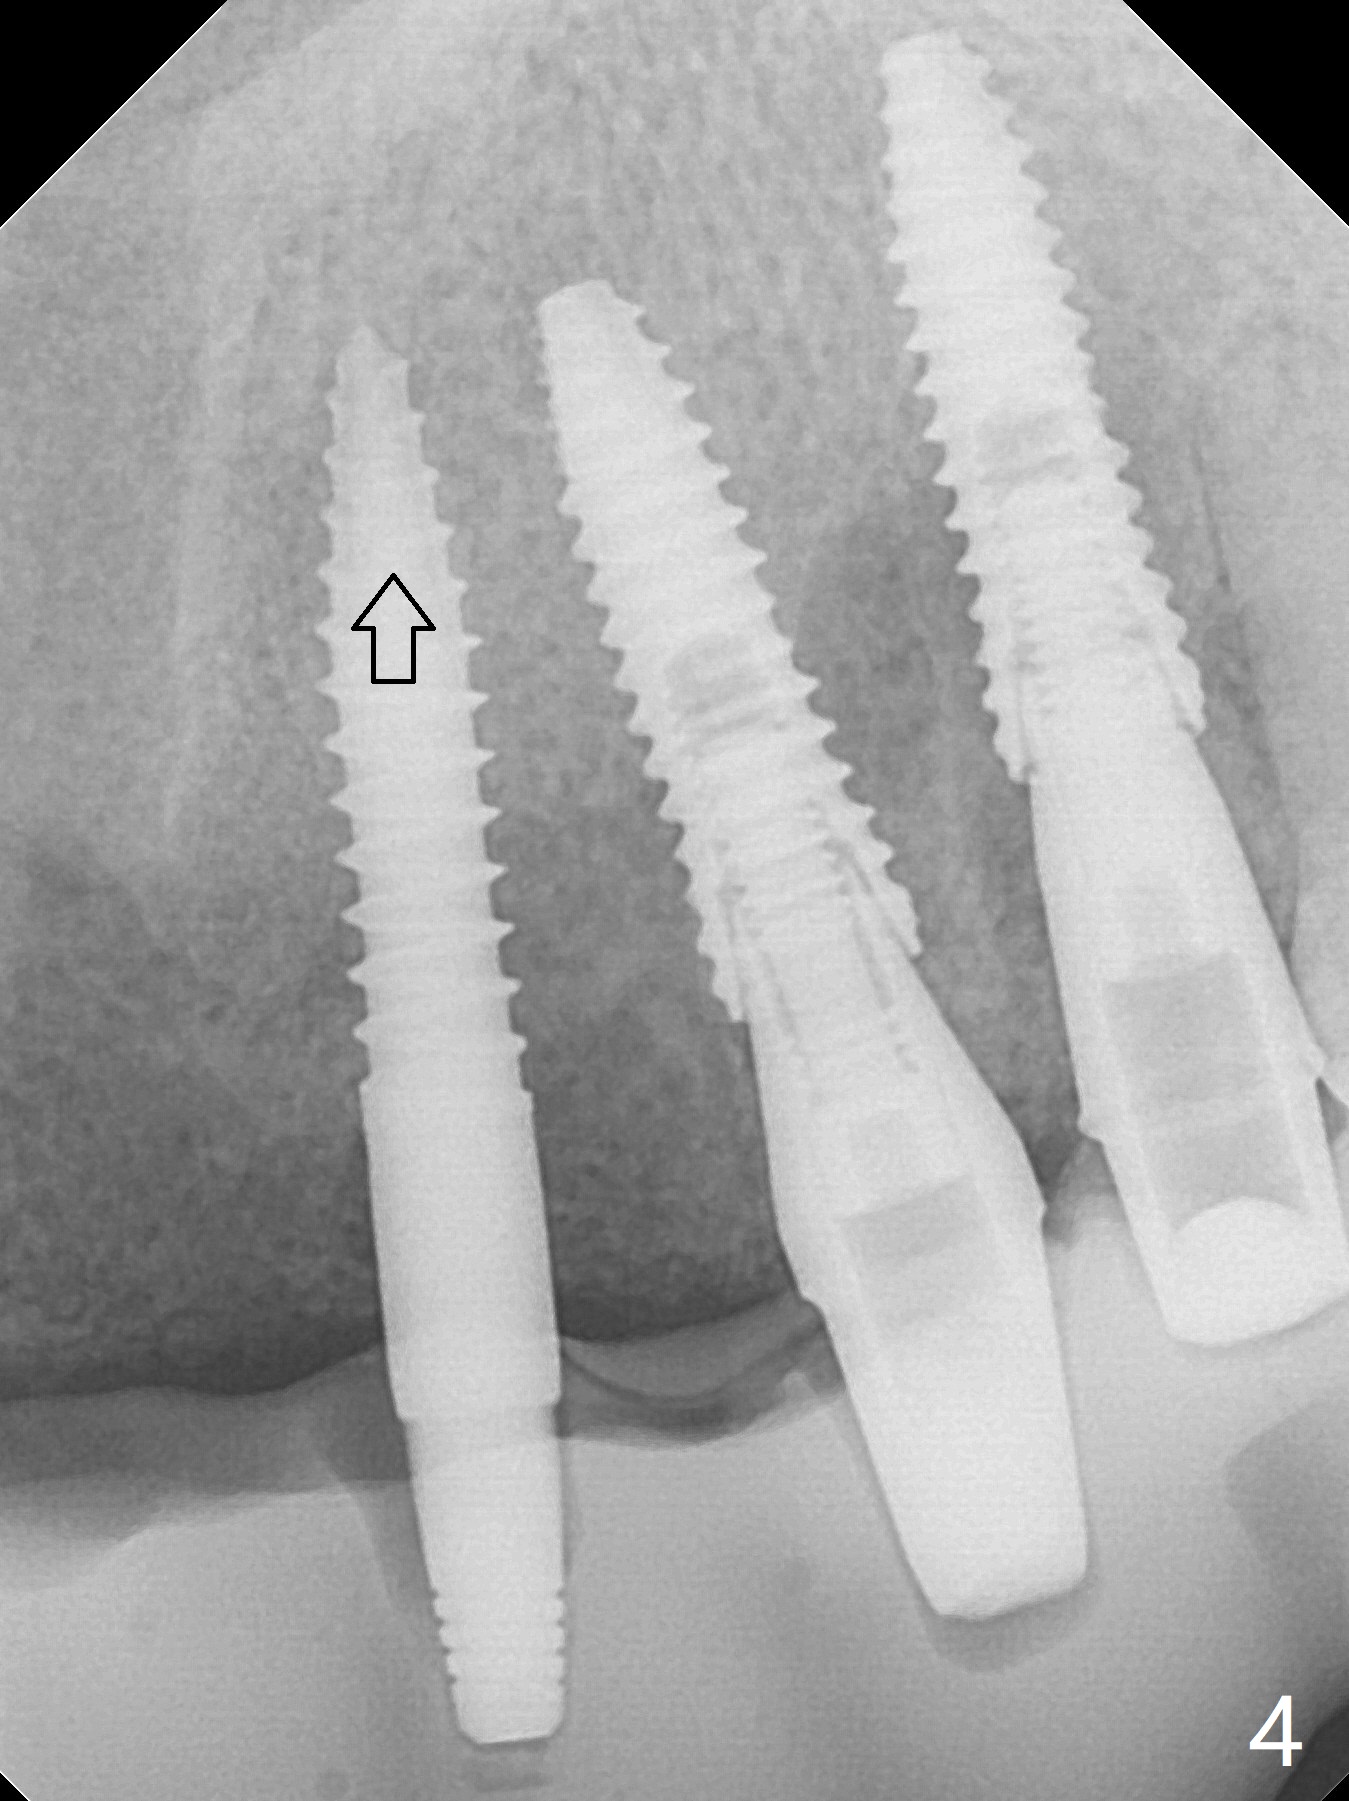

It is smooth and quick to finish osteotomy with guide at #6,7,10-12, but when 3 mm 1-piece implants are placed free hand at #7 and 10 (Fig.1,2), the gingival parts of the abutments contact the incisal edges of the lower incisors (anterior deep bite) in spite of effort to change the trajectory by repeated back and forth placement after use of Lindamann bur buccally. Following an immediate provisional (Fig.3,4), the occlusal surface of the posterior teeth are raised to eliminate anterior restoration interference. Immediate postop CBCT shows that the implants at #7 and 10 could be placed more buccally (Fig.6,7, as compared to the normal position at #6,11,12 (Fig.5,8,9)). Fig.10 was taken 2 days preop, while Fig.11-13 postop. Can we change 1-piece implants (3mm) at #7 and 10 to 2-piece one (3.5) and use angled or cementation abutments for easy restoration (Fig.14-16)?